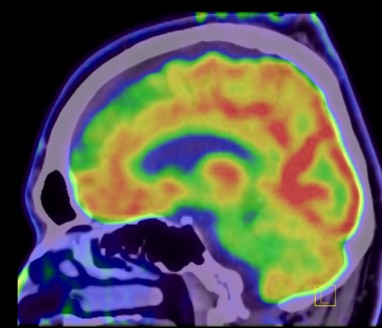

Method: A 37-year-old man with history of controlled Epilepsy who suffered from the subacute onset of cerebellar ataxia and uncontrolled seizures. Abnormalities was found in the cerebellum on initial brain MRI (Fig1,2) and we performed lumbar puncture and other neurological test included infectious, vascular and immunological which were negative. Oligoclonal bands were positive and Cerebral Pet showed cerebellar, frontal hypometabolism and focal hypermetabolism suspect thyroid nodules (Fig 3).

PET bi frontal and cerebellum hypometabolism